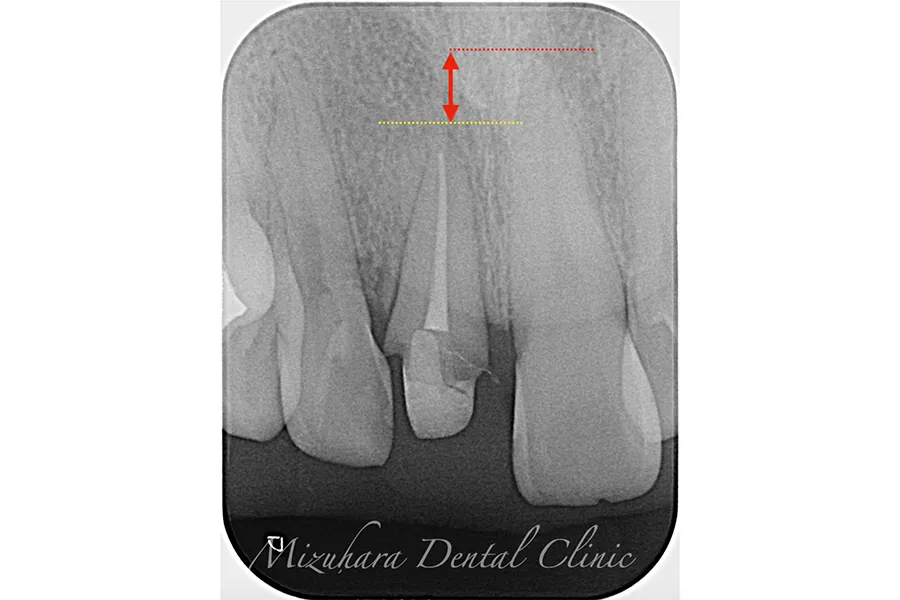

CASE.1

治療前

治療中

治療後

| 担当医 | 水原 翔 |

| 主訴 | 左下の奥歯が腫れて、揺れてる。 抜歯するしかないと言われたが、他に方法がないか相談したい。 |

| 期間 | 精密根管治療:2回 再生療法:1回 被せ物:2回 |

| 費用 | 379,500円 (精密根管治療:132,000円+支台築造:22,000円 +再生療法:110,000円+レーザー:5,500円+被せ物:110,000円) |

| 治療内容 | 精密根管治療 再生療法(歯周病によって骨が無くなった部分に骨を足す治療) 被せ物:オールセラミッククラウン |

| 治療に伴うリスク | 術後は痛み、腫れ、などの副作用が生じる場合があります。 症状が再発する可能性があります。 |